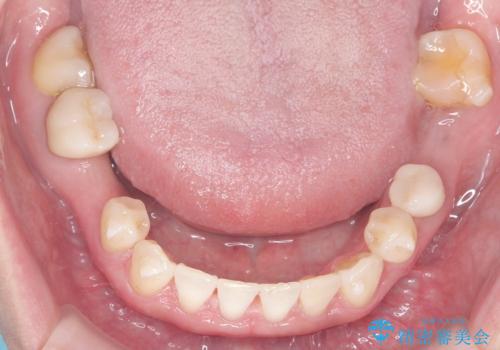

- 歯と歯の間に大きなスペースがある「空隙歯列(すきっ歯)」と、一部の歯が欠損していることによる噛み合わせの不安定さを主訴にご来院されました。

精密検査の結果、全体の隙間を閉じるだけでは適切な咬合バランスが得られないため、まずはインビザラインを用いて歯の位置を理想的な場所へと整える計画を立案しました。矯正によって欠損部位に適切なスペースを確保した後、その部分にインプラントを埋入することで、審美性と機能性の両立を目指しました。

治療は、まずインビザラインを使用して全体の隙間を閉じつつ、将来インプラントを入れるためのスペースをミリ単位で精密に調整しました。マウスピース矯正は、歯の移動量をデジタルで管理できるため、最終的な被せ物の大きさに合わせた理想的な位置取りが可能です。